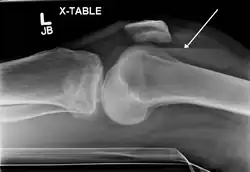

![]() | |

| Lipohemarthrosis (blood and fat in the joint space) seen in a person with a subtle tibial plateau fracture. The arrow indicates a fluid level between the upper fat component and the lower blood component. | |